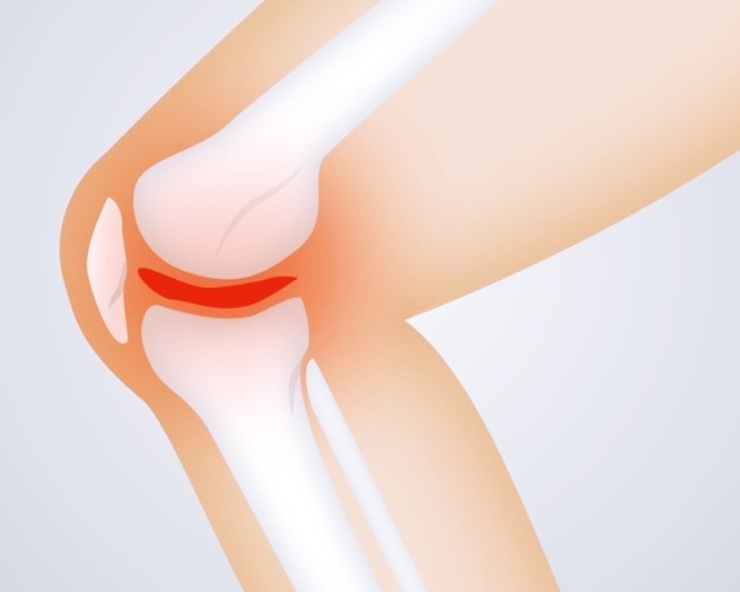

3. 계단을 오르거나 걸을 때 무릎이 아프다

퇴행성 관절염의 초기 신호 중 하나는 계단을 오르내릴 때 무릎이 뻐근하거나 통증이 느껴지는 것입니다. 관절을 움직일 때 연골이 마찰을 줄여야 하지만, 연골이 손상되면서 뼈끼리 부딪히는 느낌이 들 수 있습니다.

평지에서는 괜찮지만 계단을 오르거나 앉았다 일어날 때 통증이 심해진다면 관절염 초기 단계일 가능성이 높습니다.